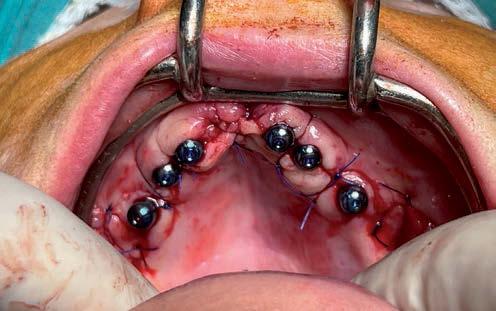

Carga inmediata en fracaso de implantes. Con implantes BLX cigomáticos Straumann Zaga Flat®️ y protocolo

Di gitalArch®️, por e l Dr. Luis Cuadrado de Vicente y cols.